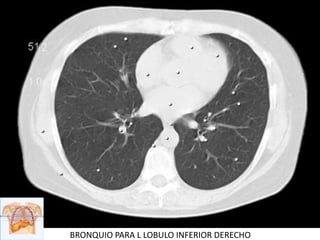

TRAQUEA: REDONDA U OVALADA, PARED DELGADA,

APLANADA, DELINEADA INTERNAMENTE Y EXTERNAMENTE

CARINA

T5

BRONQUIO PARA EL LOBULO

SUPERIOR DERECHO

BRONQUIO INTERMEDIARIO DERECHO

BRONQUIO PARA EL LOBULO MEDIO

BRONQUIO PARA L LOBULO INFERIOR DERECHO